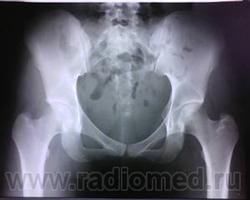

Рентгенография 02.07.12 (лежа, носки вместе, пятки врозь) http://s003.radikal.ru/i202/1207/b1/1e6a13b7bf78.jpg

тута стадия 3 наличи ренгтен прозрачной линии (признак полумесяца ) ,положение А-медиальное. на кт необходимо определить распространенность уплощения головки в милиметрах(классификация ARCO) .для стадирования на более ранних стадиях необходимо было сделать радионуклидное исследование.а так диагноз поставлен точно

3-я стадия АНГБК? Собственно сейчас болей в паху нет (около недели), есть периодическая слабая боль в области большого вертела и по передней пов-ти н/3 бедра, плюс парестезии в голени и стопе. Неврологи подозревают грыжу диска L5-S1. Уважаемые рентгенологи, может кто-то еще высказать мнение? Спасибо.